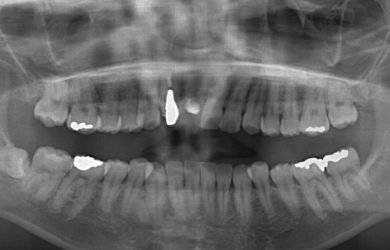

| 主訴 | 右上1番目の前歯を1週間位前に他の歯科医院で抜きました。右上2番目の前歯も高校生の時に神経を抜き被せものをしました。ブリッジにするかインプラントにするか迷っています。 | ||||||||||||||||||||||||||||||||

| 治療方針 | 抜歯した部分の骨が薄いため、そのままではインプラントを埋入出来ないため、GBR法と併用して、自分の骨を薄い部分に移植し、骨のボリュームを確保し、且つインプラント手術を同時に行うことにより、患者様にかかる外科的負担を軽減、治療期間を短縮する。 |

| 治療内容 | インプラント1本(GBR+自家骨移植)、メタルボンドセラミック2本 | ||||||||||||||||||||||||||||||||